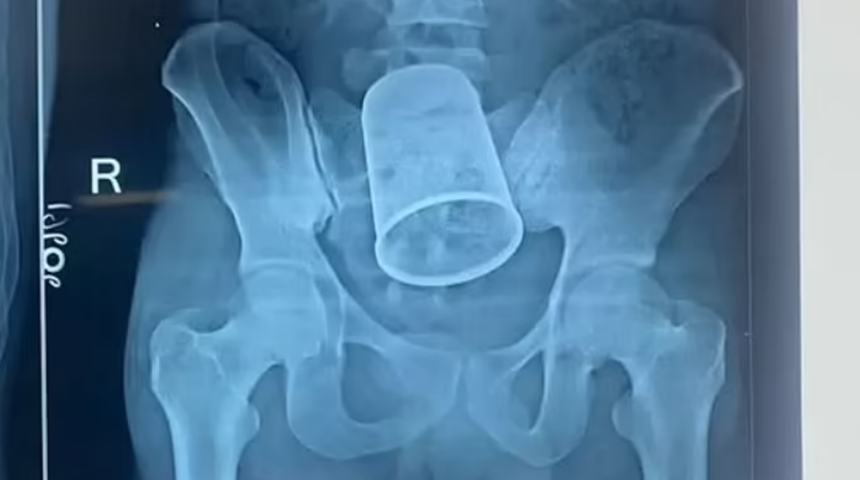

Hindistan'da yaşayan 22 yaşındaki Ritesh Kumar, 4 Ekim tarihinde rektum kanaması ve yaşadığı ağrılar nedeniyle hastaneye başvurdu. Yapılan taramaların ardından ağrının ve kanamanın nedeninin anüsten sokulan çelik bardak olduğu öğrenildi. 14 cm (5.5 inç) uzunluğunda olan bardağı vücudunun içinden çıkarmak için iki buçuk saat süren ameliyata alındı. Ameliyatı yöneten Dr Indra Shekhar Kumar, prosedürün riskli olduğunu ancak 11 doktordan oluşan bir ekibin kupayı güvenli bir şekilde çıkardığını söyledi.

Bay Kumar'a, yaralarının iyileşmesi için bağırsağın bir kısmı kesilip bir stoma torbası takıldığında kolostomi verildi. Doktorlar onu önümüzdeki hafta taburcu etmeyi hedefliyor ve Ocak ayında kolostomisini tersine çevirecek. Kupayı anüsüne soktuğunda sarhoş olduğunu ve ne olduğunu hatırlamadığını iddia ediyor.

Cerrah ekibinin bir parçası olan kıdemli bir asistan olan Dr Kumar Vaibhav Sharma Hindustan Times'a şunları söyledi: 'Çelik cam hastaların anüsüne yerleştirildi. Bu çok nadir bir vaka, çoğunlukla psikiyatri hastalarında veya sarhoş olanlarda görülüyor.

Cerrahlarımız, hastanın hastaneye yatırılmasından sonraki birkaç saat içinde sabah saat 4'te karnından ameliyatı gerçekleştirdikten sonra metal camı çıkardılar.'